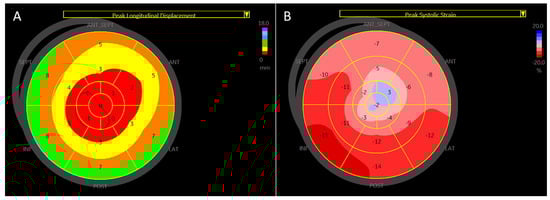

An example of a visual plot of longitudinal displacement and strain in a 48-year-old patient with moderate left ventricular dysfunction is shown in Figure 7.

In this study, we found that global longitudinal displacement like longitudinal strain is reduced significantly in patients with left ventricular dysfunction, adding new insights into the pathophysiology of myocardial contraction. A visual plot of longitudinal displacement (Figure 6) can provide additional insight into myocardial function assessment.

Figure 7. A visual plot of peak longitudinal displacement and strain in a 48-year-old man with anterior myocardial infarction and an ejection fraction of 35%. (A) Peak longitudinal displacement is very low (around 0) in the apical region (red), consistent with extensive apical myocardial infarction and involvement of other myocardial walls. Higher displacement is observed in the infero-posterolateral segments (green and brown). The average global longitudinal displacement is 3.4 mm. (B) Peak longitudinal strain is also very low in the corresponding apical segments, with better strain observed in the postero-lateral wall. The global longitudinal strain is −8.1%.